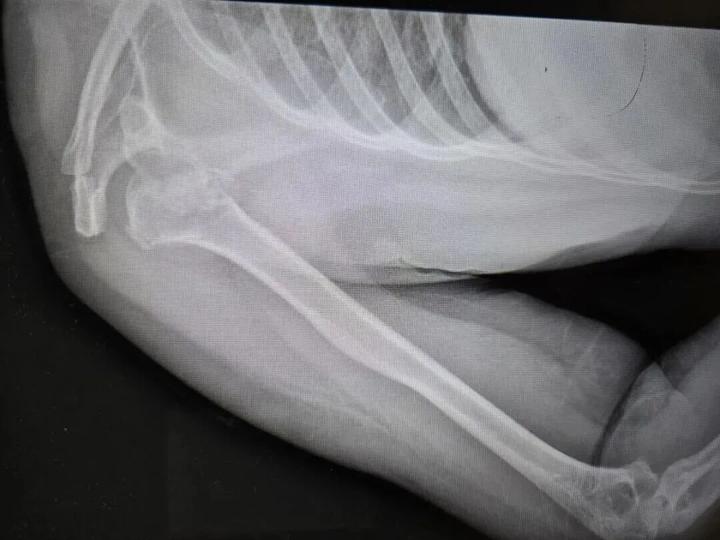

近日,河南50岁的张大姐在睡梦中粉碎性骨折,肩膀骨头碎成七八块,丈夫称妻子全程都在床上躺着。

河南省人民医院创伤骨科主任刘涛称:“第一反应不敢相信,高空坠落、车祸撞击才会有这么大的力。”像张大姐这样癫痫导致粉碎性骨折临床及文献中都极罕见。

诊疗小组制定方案,将劈裂的肱骨骨头、后脱位等四大部分、七八块碎裂的骨头都按原貌实现完整复位,并将受损的肌腱完全修复,将塌陷的部分填充了支撑骨。目前,张大姐正在进一步接受癫痫相关管理与规范治疗。

随后,神经内科团队通过脑电图监测,终于捕捉到了真相:张大姐在夜间癫痫发作时,大脑异常放电导致全身肌肉产生猛烈、极端的收缩。在那一瞬间,肌肉牵拉的力量通过杠杆作用,竟生生将她的骨头“震”碎并挤出了关节窝。